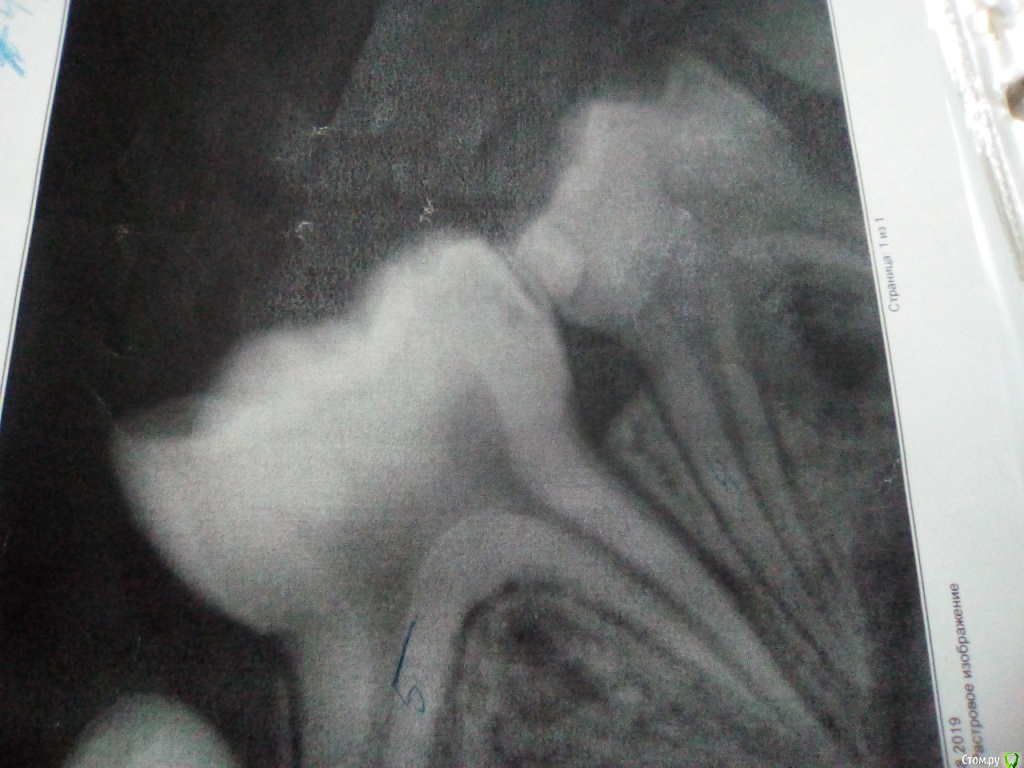

asie84 Опубликовано 2 сентября, 2019 Поделиться Опубликовано 2 сентября, 2019 Добрый день.Ребенку 6 лет.Были на осмотре у стоматолога, попросила посмотреть состоянии пломб на контактах между 4ми и 5ми снизу на обеих сторонах.На визуальном осмотре стоматолог ничего не отметила (о наличии проблем), сделали по моей просьбе рентген (рентген прилагаю, извините за качество, это распечатка).Так и не поняла есть ли там кариес или нет, стоматолог за лечение ничего не сказала, а на снимках какие то затемнения, боюсь упустить зубы(.Особенно волнует, что за темная полоса под пломбах на одной из четверок.Если вас не затруднит, посмотрите пожалуйста снимки Ссылка на комментарий

krokomot Опубликовано 3 сентября, 2019 Поделиться Опубликовано 3 сентября, 2019 Кариес есть, пломбы переделать, использовать зубную нить, чистка на ночь обязательно, поменьше сладкого. Ссылка на комментарий